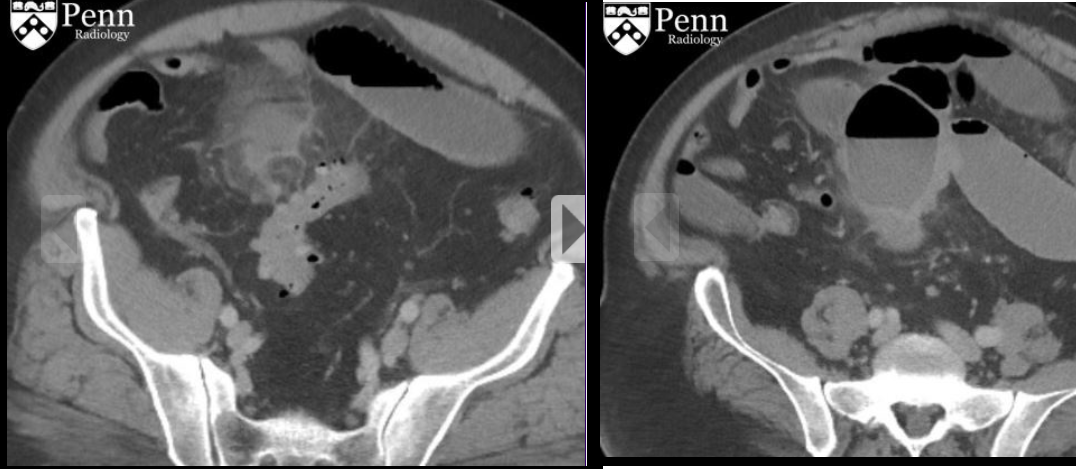

64 anos, mulher com Dor abdominal intensa

Hérnia de spiegel com sinais de estrangulamento

Colo herniário na linha semilunar, separando os músculos reto abdominal e transverso

Hérnias de spiegel tem alto risco de encarceramento (margens afiadas).

Neste caso a hérnia continha gordura omental e mostrava sinais de estrangulamento: densificação da gordura e liquido no interior do saco herniário.